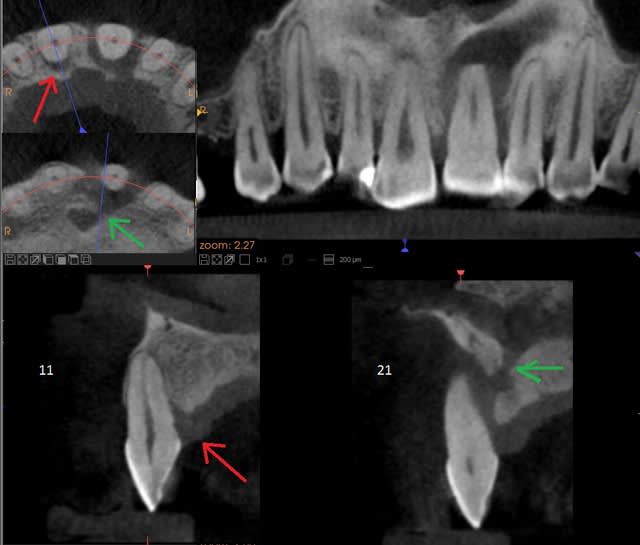

1 : Pensez vous que la cause de la lésion soit occlusale, justement ( cela aurait pu débuter comme sur la 11, flèche rouge ) ?

2 : quid de la jonction avec le canal nasopalatin ( flèche verte ) ?

L'apex est atypique au scann, je pense qu'il n'y a plus de vascularisation ici.